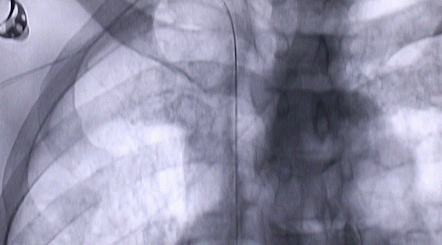

1月12日,西安國(guó)際醫(yī)學(xué)中心醫(yī)院心臟外科郭穎強(qiáng)主任團(tuán)隊(duì)成功為一名腹主動(dòng)脈閉塞、右側(cè)腎動(dòng)脈閉塞、左側(cè)腎動(dòng)脈重度狹窄、腹壁淺表動(dòng)脈側(cè)支循環(huán)形成、高血壓病3級(jí)(極高危組)合并閉塞性周?chē)鷦?dòng)脈粥樣硬化、急性腎功能不全的老年患者實(shí)施腎動(dòng)脈球囊擴(kuò)張 腎動(dòng)脈支架植入術(shù) 動(dòng)脈血栓抽吸術(shù) 髂動(dòng)脈開(kāi)通術(shù),治好了困擾患者多年的頑固性高血壓?;颊吣壳翱祻?fù)良好,將于近日出院。

按照術(shù)前制定的方案,郭穎強(qiáng)主任和楊金保博士首先嘗試開(kāi)通閉塞的右腎動(dòng)脈,但由于血栓機(jī)化、鈣化嚴(yán)重,右腎動(dòng)脈難以開(kāi)通。遂謹(jǐn)慎擴(kuò)張狹窄的左腎動(dòng)脈,并成功植入一枚支架。之后經(jīng)過(guò)反復(fù)旋磨、抽吸,順利開(kāi)通髂動(dòng)脈,但腹主動(dòng)脈閉塞段仍難以擴(kuò)通。此時(shí),患者居高不下的血壓很快恢復(fù)到正常水平。